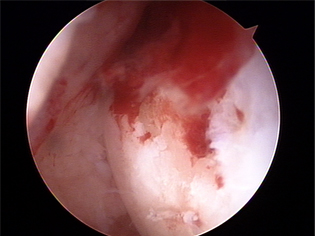

대부분 관절경으로 치료하며, 변연절제술을 하게 됩니다. 일시적인 효과는 있지만 퇴행성 진행을 지연시키지 못해 통증이 재발하기 쉬우며 관절염이 더 빨리 진행 할수도 있습니다.

미세천공술 2